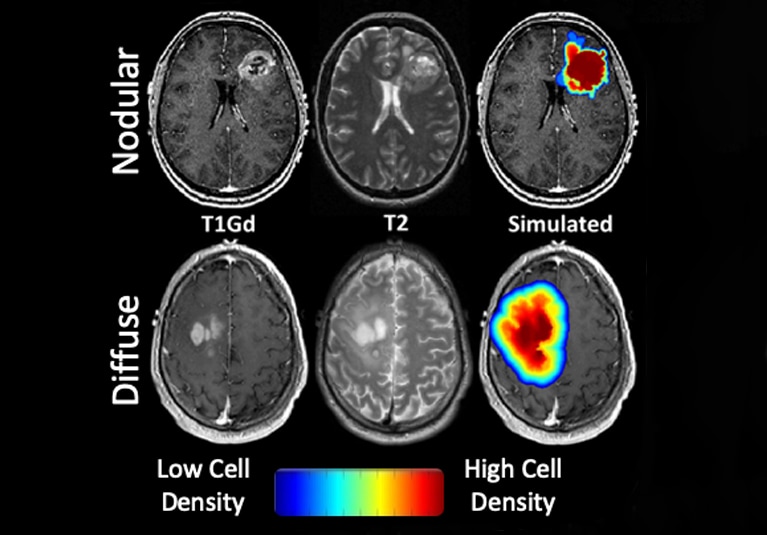

76. April 26, 2024

AI helps map glioma heterogeneity

Mayo Clinic researchers are using AI to create a system that predicts glioma biology based solely on imaging. The goal is to better personalize cancer treatment.